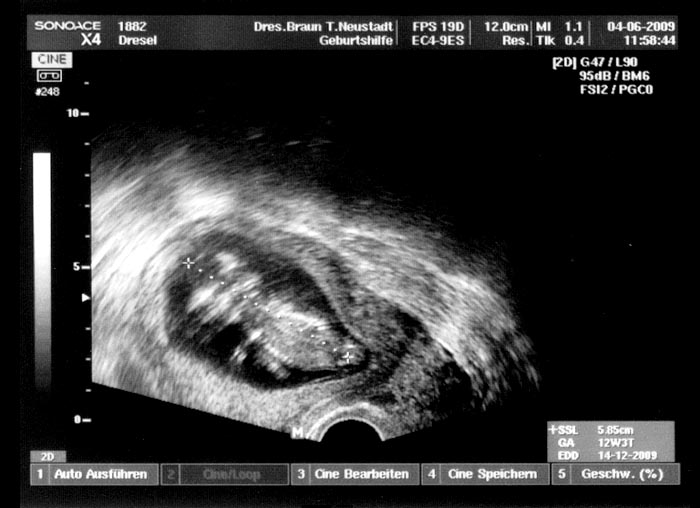

5. Ultraschallaufnahme